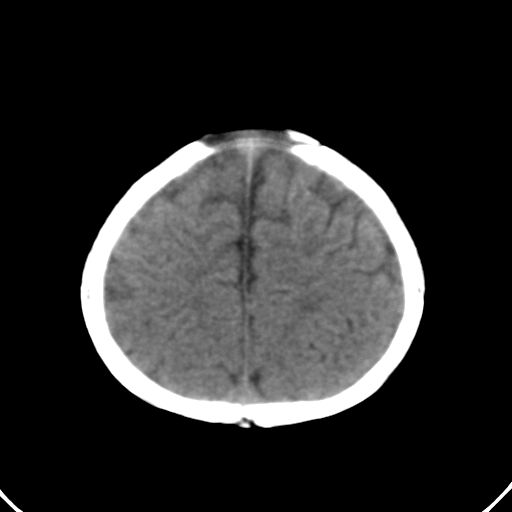

男,10月,足月剖腹产,无缺氧病史,当时评分均正常,学走路时脚后跟不着地!

小孩子片子,看得少,请各位老师看看有问题没?

未见明显异常。

外部性脑积水

考虑外部性脑积水

轻度脑外脑积水表现.